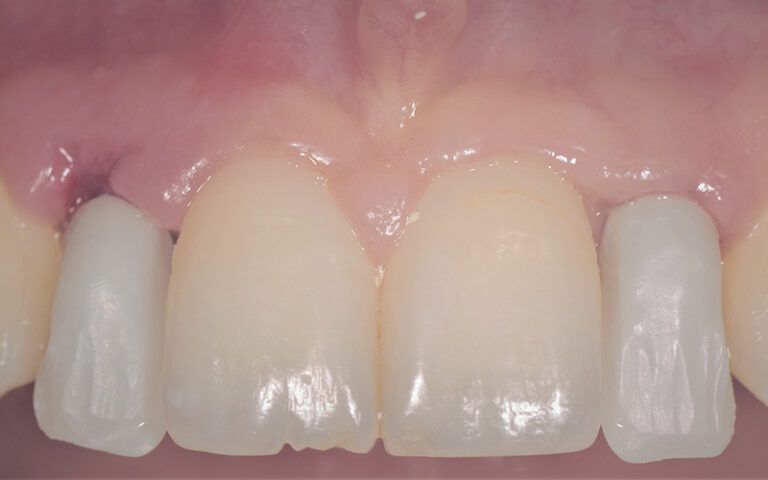

After a few days, the pertinent x-ray and clinical controls were carried out and the two crowns were definitively cemented, completing the restoration of the agenesis of the two lateral incisors 12 and 22.

Definitive Zr crowns post-load